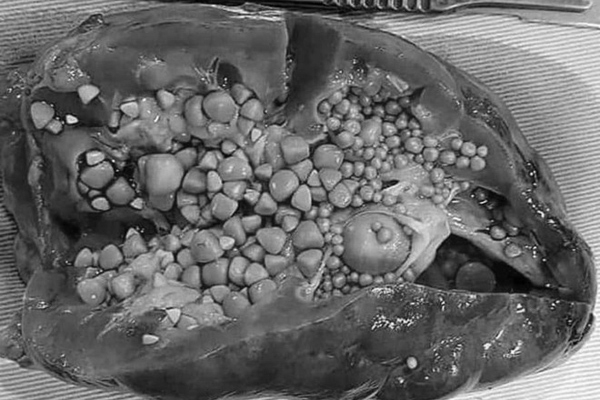

Sỏi tiết niệu là bệnh lý rất phổ biến, nếu để lâu, nhu mô thận sẽ bị giãn mỏng, mất chức năng

Trong nhiều chục năm làm nghề, PGS Thành chia sẻ, đã từng phẫu thuật cho nhiều trường hợp bị sỏi thận kích cỡ lớn, tương đương quả cam, quả bưởi, nhưng nhiều năm trở lại đây, số ca bị “sỏi khổng lồ” đã giảm dần.